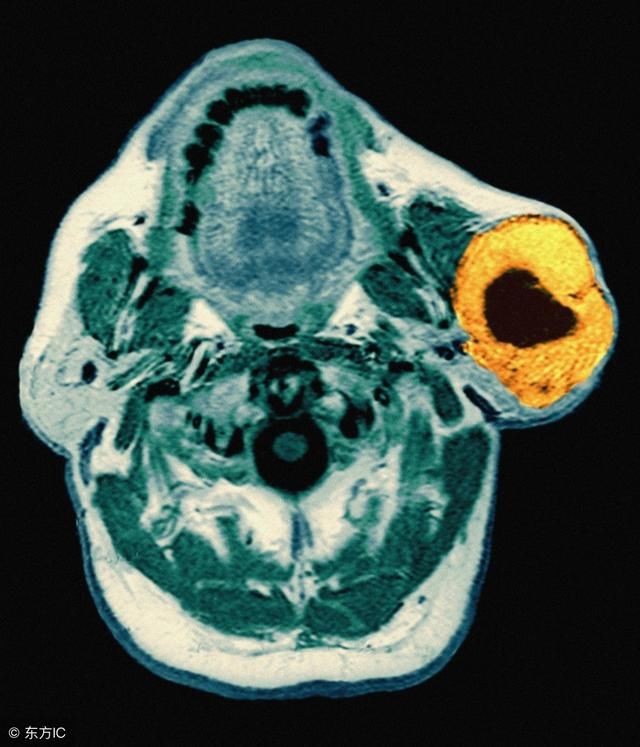

路边小店打耳洞,女子耳垂感染长出两个大肉瘤

耳垂边突然长疙瘩,别掉以轻心,可能是这种瘤